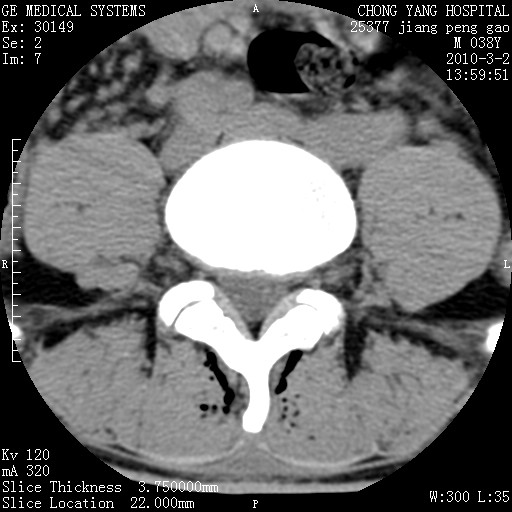

标题: CT24887:M38Y 反复腰痛 无外伤史 未做针灸 竖脊肌为何积气 [打印本页]

标题: CT24887:M38Y 反复腰痛 无外伤史 未做针灸 竖脊肌为何积气

退变,轻度增生/间盘膨出、l5椎后缘软骨结节。

肌间隙积气过多也为退变表现。